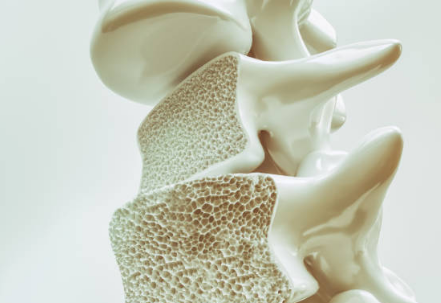

골다공증은 뼈의 밀도가 감소하여 뼈가 약해지고 쉽게 골절될 위험이 커지는 질환입니다. 주로 노화, 영양 부족, 생활습관, 유전적 요인 등 다양한 원인에 의해 발생하며, 초기 증상이 거의 없어 "조용한 질환"이라고 불리기도 합니다. 이로 인해 골다공증은 예방과 조기 관리가 매우 중요한 질환으로 인식되고 있습니다.

골다공증은 골밀도가 저하되어 골이 부드럽고 턆터져서 골절이 쉽게 일어날 수 있는 상태입니다. 정기적인 검진과 건강한 생활습관이 중요합니다.

골다공증의 주요 원인은 뼈의 손실과 혈액 순환 문제입니다. 뼈의 손실은 뼈의 교체 속도가 뼈 손실 속도를 넘어서는 경우에 발생합니다. 혈액 순환 문제는 뼈에 필요한 영양분과 산소를 제공하는 혈액의 흐름이 부족할 때 발생합니다.